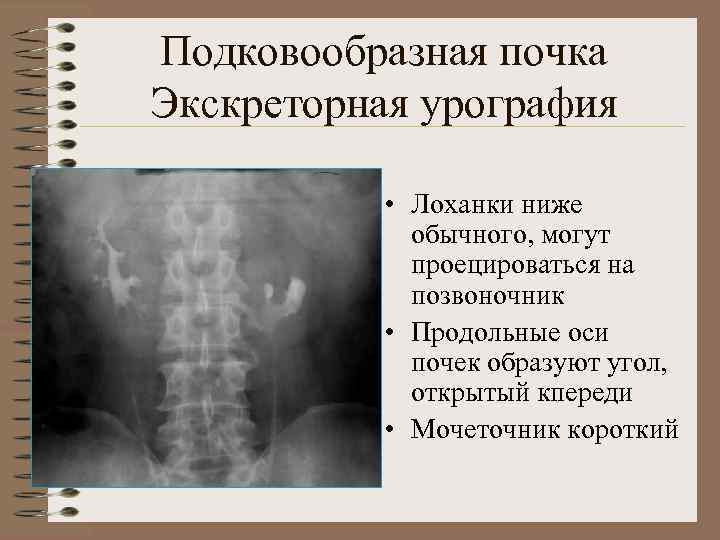

Подковообразная почка Экскреторная урография • Лоханки ниже обычного, могут проецироваться на позвоночник • Продольные оси почек образуют угол, открытый кпереди • Мочеточник короткий